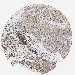

LIVER CANCER - Protein expressioni

A mouse-over function shows sample information and annotation data. Click on an image to view it in a full screen mode. Samples can be filtered based on level of antibody staining by selecting one or several of the following categories: high, medium, low and not detected. The assay and annotation is described here.

Antibody stainingi

Antibody staining in the annotated cell types in the current human tissue is reported as not detected, low, medium, or high, based on conventional immunohistochemistry profiling in selected tissues. This score is based on the combination of the staining intensity and fraction of stained cells.

Each image is clickable and will lead to virtual microscopy that enables deeper exploration of all samples and also displays staining intensity scores, fraction scores and subcellular localization as well as patient and tissue information for each sample.

Antibody HPA008208

Antibody HPA011389

Staining

High

Medium

Low

Not detected

Intensity

Strong

Moderate

Weak

Negative

Quantity

>75%

75%-25%

<25%

None

Location

Nuclear

Cytoplasmic/membranous

Cytoplasmic/membranous,nuclear

Cholangiocarcinoma

Carcinoma, Hepatocellular, NOS